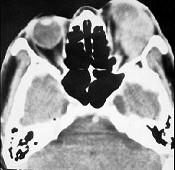

问题 男性45岁,左眼疼痛伴视力下降1个多月,左眼明显外突,CT扫描如图所示,最可能诊断为()

选项 A.左侧眶内炎性假瘤 B.眶内血管瘤 C.眶内纤维瘤 D.眶内结核 E.眶内转移瘤

答案 A